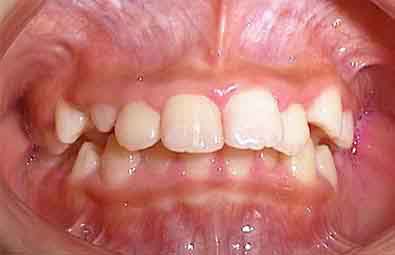

初診の状態